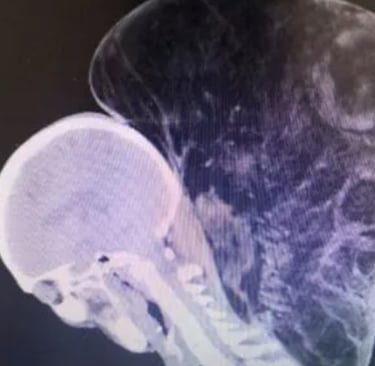

The photos — which you shouldn’t look up over breakfast — show a man whose neck bulges outward like a swollen balloon. It’s soft, rounded, not malignant or monstrous in the cinematic sense. Just there. Lurking in plain sight, tolerated the way we tolerate slow internet or chronic back pain or governments that barely function.

Medical experts who examined the case noted that lipomas can reach enormous sizes when left unchecked. The body doesn’t see them as threats, so the immune system shrugs. The man’s was roughly the size of a basketball, weighing nearly fifteen pounds. It had its own blood vessels — a freeloading roommate metabolically tethered to him.